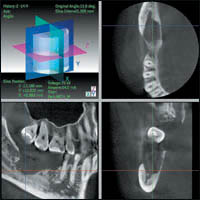

— расширяет возможности в диагностике височно-нижнечелюстных суставов, наружного слухового прохода, среднего и внутреннего уха (рис. 8).